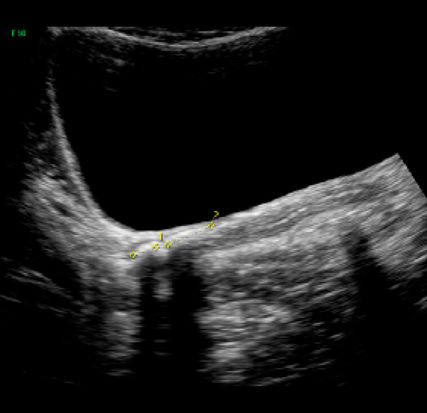

Abb. 4: Verkalkte Deflux®-Depots. Ein häufiges Bild einige Jahre nach Ostium-Unterspritzung, sonografisch von einem Stein nicht zu unterscheiden. Die Anamnese führt zur Diagnose. In Einzelfällen mit gleichzeitig erweitertem Harnleiter ist eine ureteroskopische Klärung notwendig. Denn ein Deflux-Depot kann in Einzelfällen auch nach Jahren obstruktiv werden

Hier ist die Vorgangsweise wie bei Erwachsenen: Spontanabgang abwarten. Bewegung, NSAR, Alphablocker (Silodosin 1 x 4mg ab 4 Jahren bzw. 20kg, „off-label“, aber erste Wahl, Tamsulosin 0,4mg ab einem Alter von 4 Jahren).10 Wenn der Stein größer als ca. 10mm ist, therapieresistente Schmerzen verursacht oder nicht spontan abgeht: Double-J und/oder URS (Ch 4,5–6 Instrument). Wichtige Differenzialdiagnose: verkalkte Deflux-Depots (Abb. 4).